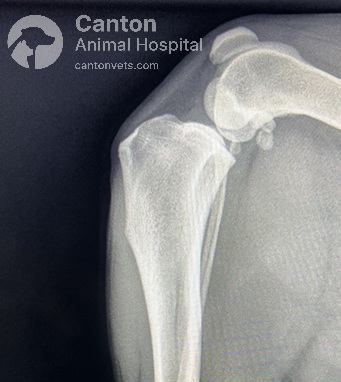

Radiographs (X-rays)

Used to rule out other causes of lameness.

Common findings in chronic or partial CCL tears:

Fat pad compression (“fat pad sign”) and joint capsule swelling due to fluid buildup.

Osteophyte (bone spur) formation on the trochlear ridge, tibial plateau, and patella.

Thickening of the fibrous joint capsule and subchondral sclerosis (increased bone density).

Tibial Plateau Leveling Osteotomy (TPLO) is a precise orthopedic procedure that requires detailed preoperative planning to achieve the best results. Before surgery, radiographs (X-rays) are taken to measure the dog's tibial plateau angle (TPA) and calculate the necessary rotation to achieve an optimal final angle of 5 to 6.5 degrees.